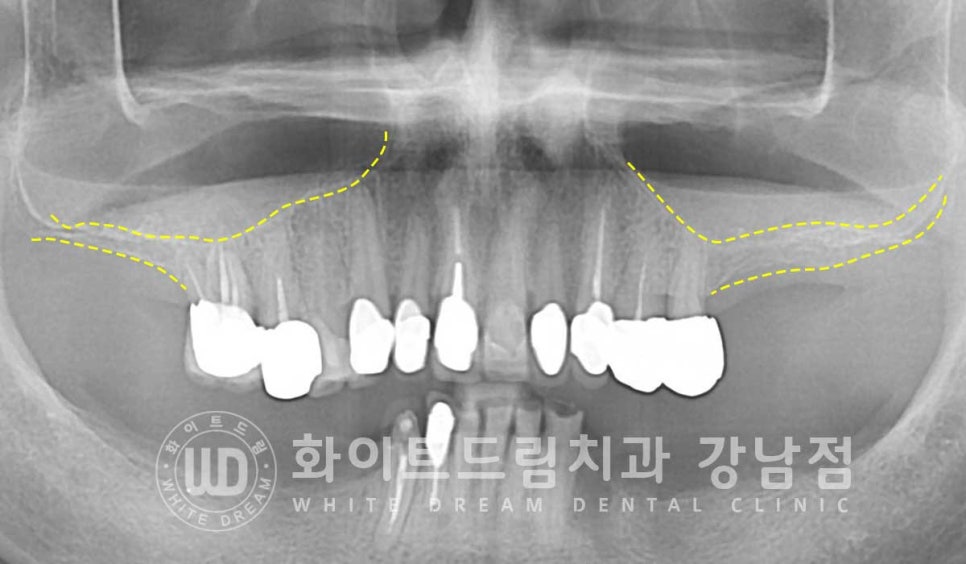

환자분의 상악동 거상 술 전의 잇몸뼈 높이와 거상 후를 비교해 보면

한눈에 어떤 부위에 대량의 뼈이식이 진행됐는지 확인하실 수 있을 겁니다.

노란색 점선이 초기 환자분의 잇몸뼈 높이이며, 거상 후 하늘색 선 만큼 상악동이 올라갔고

그 사이에 하얗게 보이는 뼈이식재가 들어간 것이 확인됩니다.